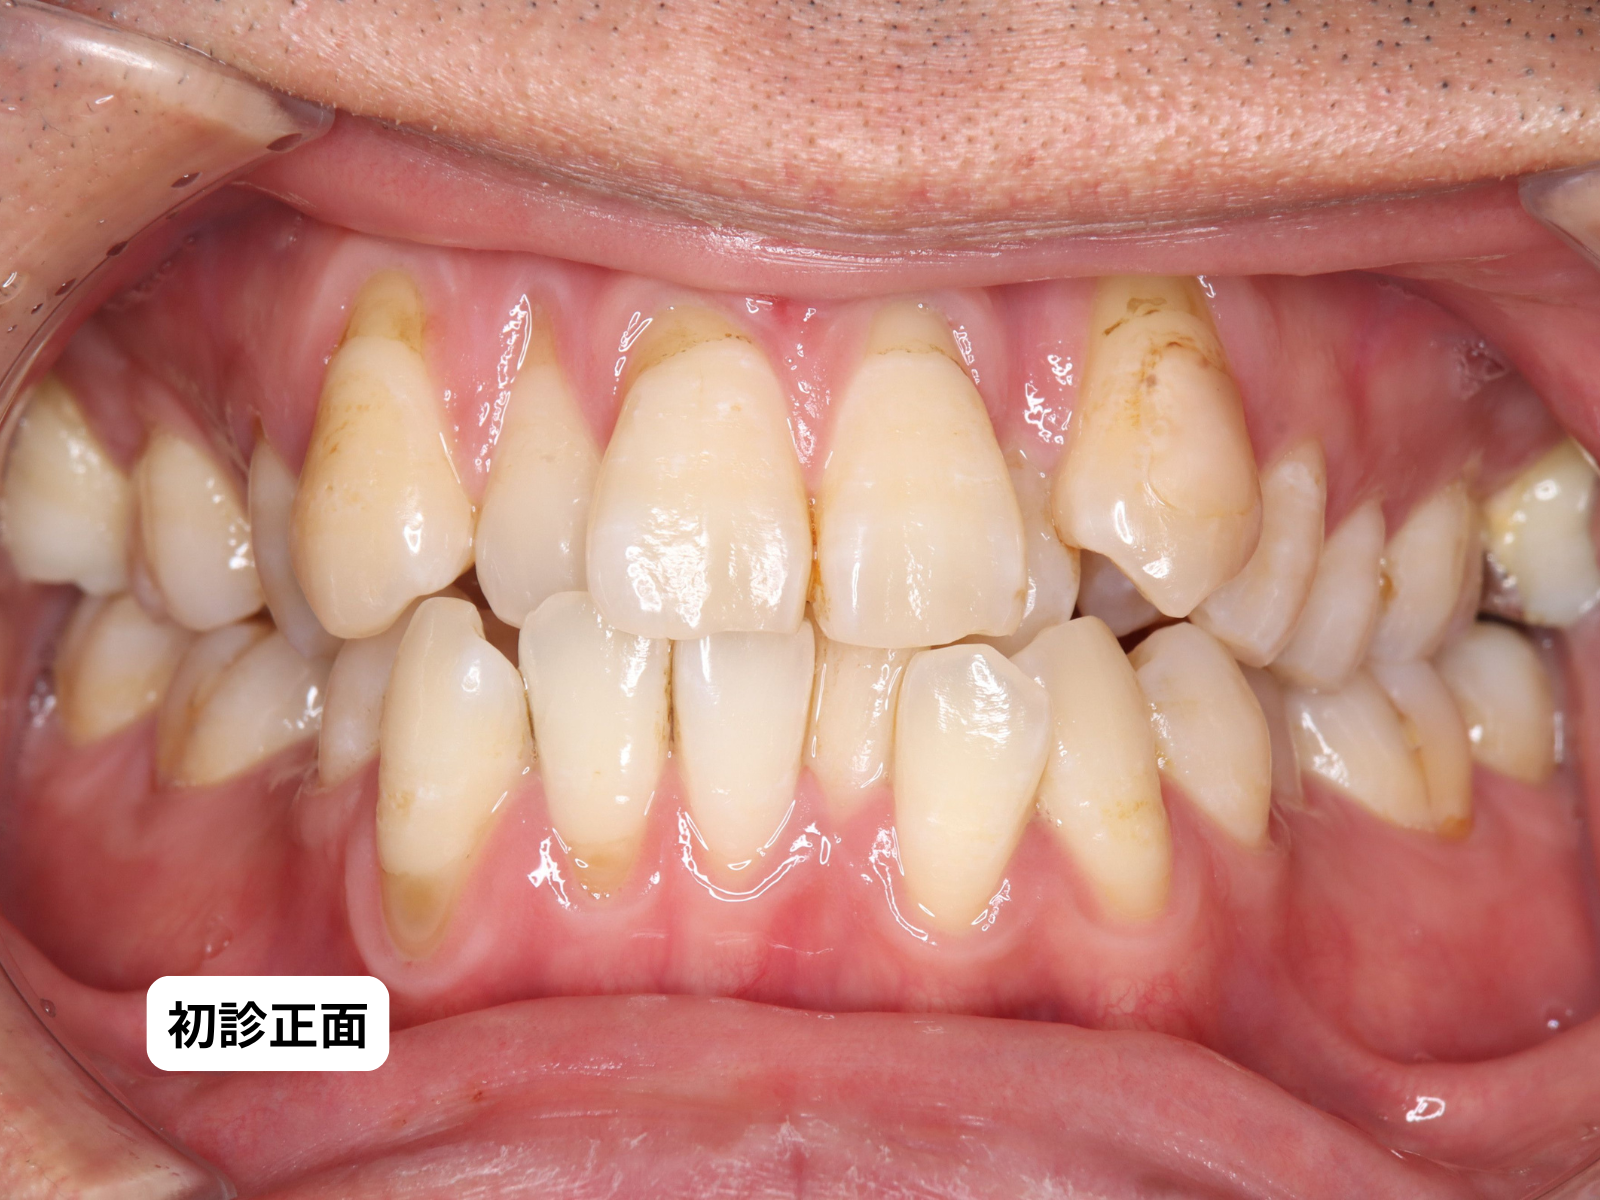

30代の男性で、歯並びのガタガタ(叢生)を主訴に来院されました。お口の中を見ると、歯並びの問題だけでなく、上下の前歯6本すべてで歯茎が下がっている状態でした。

#26-写真1 初診 正面

初診

上下の前歯の歯茎が全体的に下がり、歯根が露出